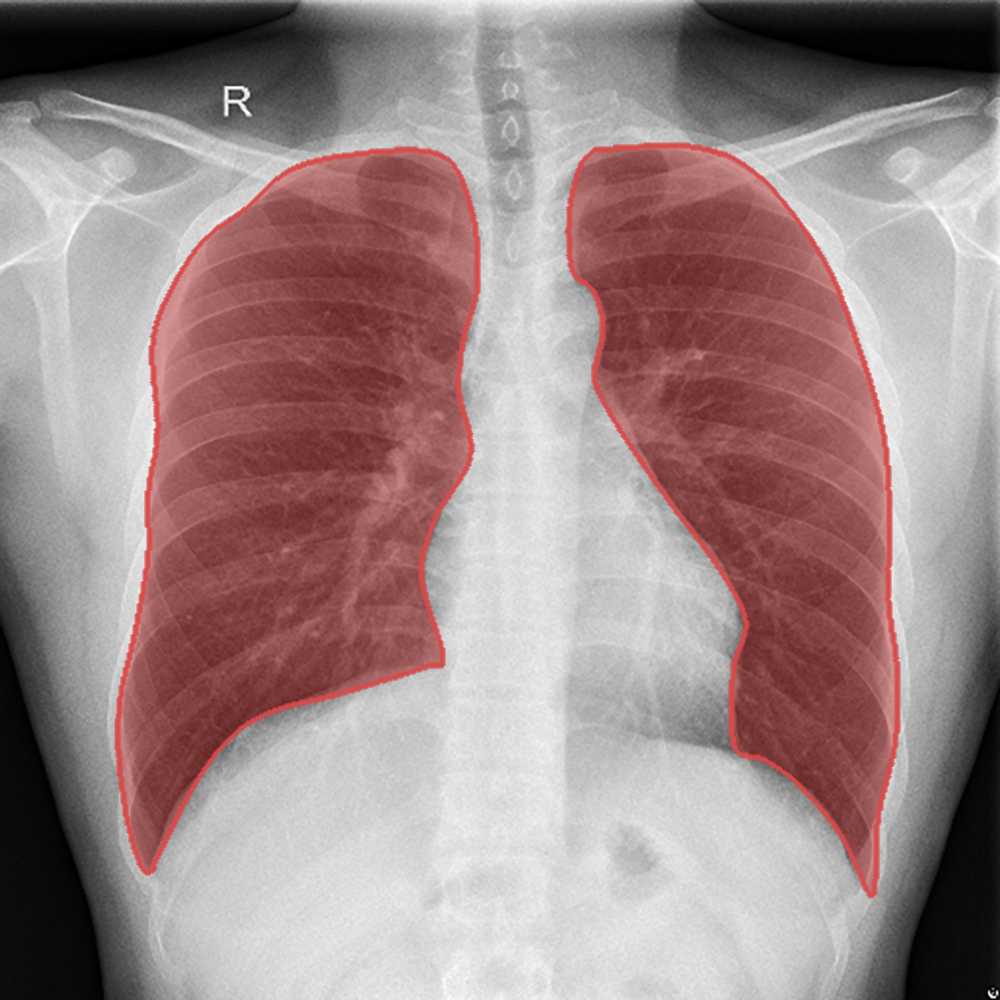

Introduction: We present a collection of lung segmentation models designed for accurate analysis of chest X-ray (CXR) images. These models have undergone rigorous training, validation, hyperparameter tuning, and testing on a diverse dataset consisting of CXRs from three publicly available sources: the Darwin, Montgomery, and Shenzhen datasets.

Segmentation example - Shenzhen.png